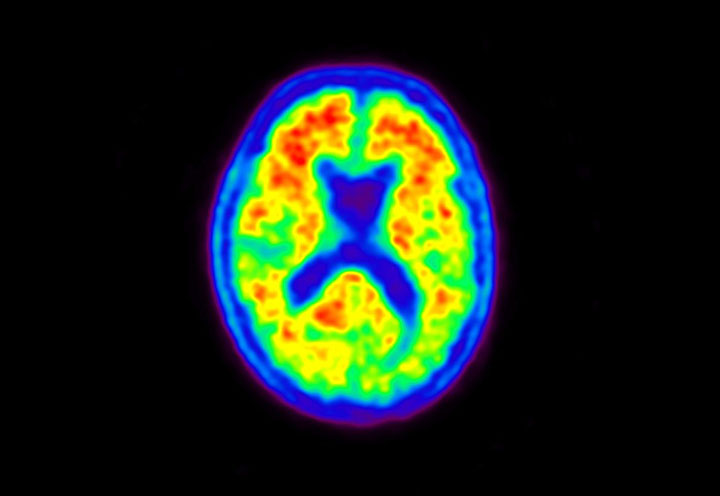

Head / Case5 : Amyloid

Courtesy : Kindai University Hospital

- Imaging protocol

- Injected dose: 4.27 MBq/kg, 18F-Flutemetamol

- Uptake time: 99 minutes

- Scan time: 20 minutes